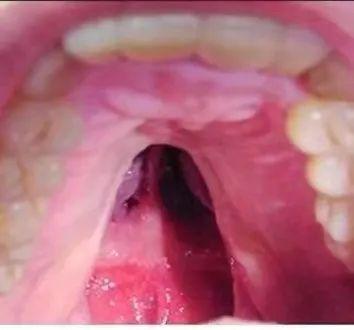

手术前 上颚裂痕

手术后